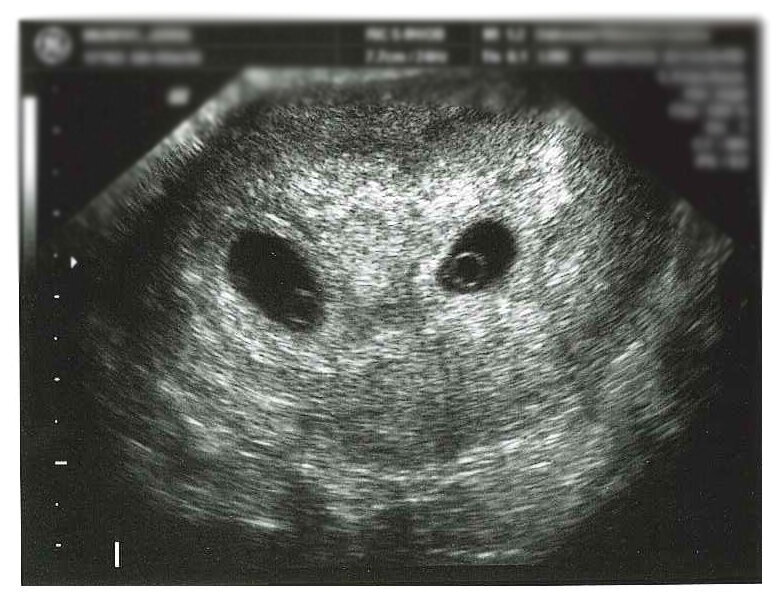

-Тогда поздравляю Вас,у Вас двойня!

Врач повернула экран ко мне и показала две маленькие точки.